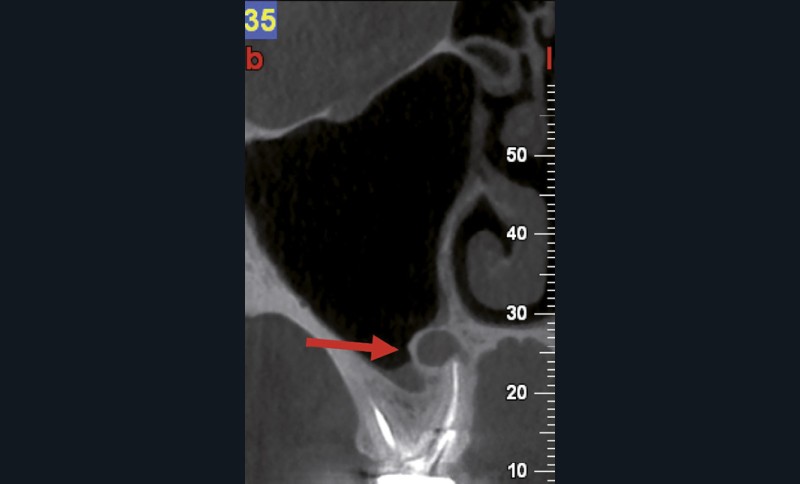

Endal, en 2011, montrait également, en utilisant le micro CT Scanner, l’insuffisance de nettoyage des isthmes inter-canalaires à nos techniques conventionnelles [19]. L’utilisation du laser Er:YAG devenait alors incontournable dans le nettoyage de ces isthmes et des zones non instrumentées (fig. 2 et 3).

Si l’étude de Peters [18] nous montre que l’instrumentation laisse 35 % du volume canalaire non instrumenté, Ricucci et Siqueira montrent que la préparation physico-chimique n’élimine que partiellement les tissus nécrotiques à l’entrée des canaux latéraux, des isthmes et des ramifications apicales, en laissant des tissus enflammés et infectés, en association avec des lésions apicales [29] (fig. 4 et 5).

Fig. 4 – Coupe d’une racine mésiale de molaire mandibulaire avec deux canaux traités. Coupe à 3 mm de l’apex, coloration Brown et Brenn, technique modifiée par Taylor. Ces images montrent un isthme étroit avec une infection bactérienne, ce qui prouve l’importance de désinfecter et d’inclure l’isthme dans les traitements conventionnels et dans les rétropréparations apicales en chirurgie endodontique.

Si les isthmes sont particulièrement mis en évidence au niveau des molaires mandibulaires, cela devient médicalement important au niveau des molaires maxillaires.

La diffusion bactérienne et de leurs toxines, au niveau des molaires maxillaires est à l’origine d’un grand nombre de sinusites maxillaires chroniques, d’origine dentaire. Celles-ci sont principalement causées par l’absence de traitement du deuxième canal MV, qui existe dans 90 % des cas, et il est à noter que ces deux canaux – MV1 et MV2 – sont également reliés par un isthme.

Le nettoyage des isthmes intercanalaires reste un réel problème, et semble responsable de nombreux échecs [43]. Par ailleurs, il est nécessaire d’utiliser des instruments qui évitent de propulser les débris, tant apicalement que latéralement, en obturant les entrées isthmiques avec des débris compactés.